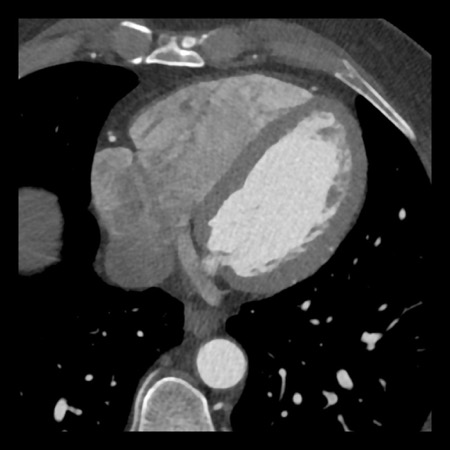

case 4 – CAD-RADS 3/P1/I+ thrombus left ventricle

First, scroll through the CTA images.

How would you describe the findings on the coronary CTA?

The findings are:

- Moderate (50-69%)

stenosis in the proximal LAD caused by a non-calcified plaque. - Variant of

sinoatrial (SA) nodal artery. The artery usually arises from the RCA as a second

branch after the conus artery, however in this case it arises from the LCX,

courses behind the aorta, anastomosing with the right atrium and with a small

branch supplies the SA-node of the heart. - Thrombus in the

apex of the left ventricle. - CTP was performed

in this patient. CTP showed a perfusion defect at stress imaging in the

territory of the LAD (I+), at rest no perfusion defect was visible.

This patient classifies as CAD-RADS 3/P1/I+, which means

this patient requires further investigation.